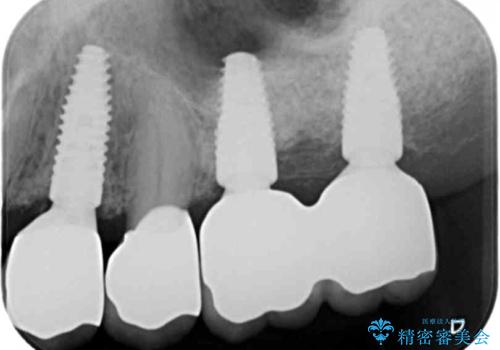

虫歯の再発による抜歯後のインプラント治療

抜歯後、骨の再生を待ったことで、清掃性の高い位置に埋入を行い機能的・審美的なインプラント治療を行うことができました。